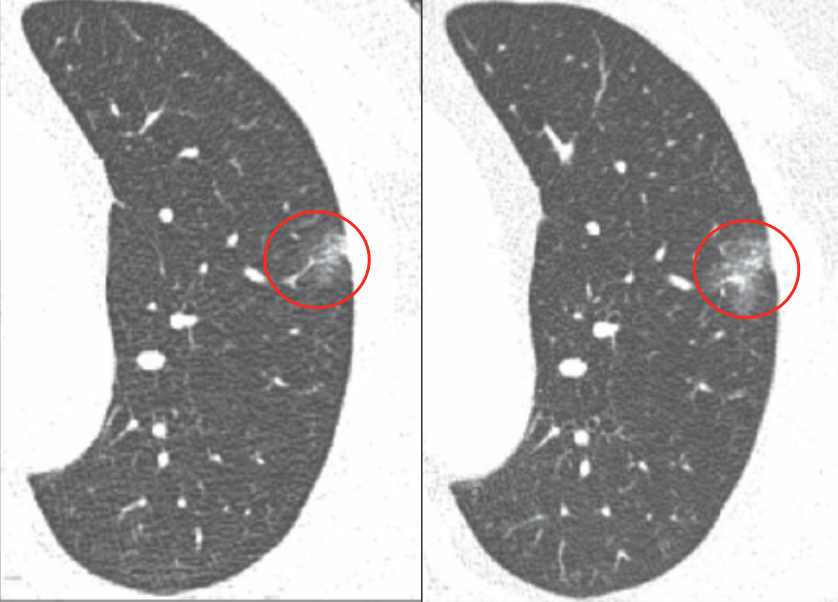

【图1】

如图1所示,左侧图片为13mm形态不规则的磨玻璃结节,里边有一些偏实性的成分,但并非是典型的早期肺癌的影像学表现。在34个月(将近3年)的随诊过程中,这个结节变大了,右侧图片的实性成分增多,考虑为肿瘤。在这种情况下,患者做了手术之后的病理显示为腺癌。

徐燕医生表示,上述病例经过了34个月的随诊,病灶在略有增长和变实的时候切除,帮助患者和医生增强了手术的信心,病灶切下来还是一个早期肿瘤,随诊所需要的时间并不意味着肿瘤就会变成晚期或者播散,所以大家不用过于担心。时间和肺内结节的变化情况也是帮助医生来判断结节性质的一个非常重要的措施。